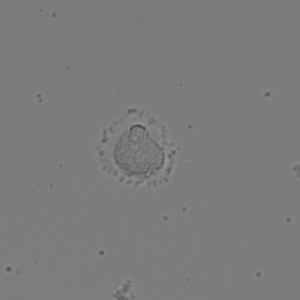

(a) Frame 1. Cell attachment phase

Figure 3: Original images of sequence is example of high dynamics of cell behavior affecting on contrast properties

The Fig.3 is representing couple of frames of sample image sequence with relatively high contrast between foreground and can be segmented with almost 95% accuracy with any method we used. Frame 1 of sample sequence presented at Fig.3(a) contain regions of hyper contrast pixels. In this case such condition does not affect on valid recognition since they are belong to object and present on margins of it and differs well from background. For Frame 2 there is absence of such pixels (Fig.3(b)) and this conditions also makes segmentation possible in relatively inflexible filtering conditions. The Frame 2 has relatively low contrast however it is seen that after filtration applied on image we achieve good difference of core and cell body compared to background as it presented at Fig.4 .